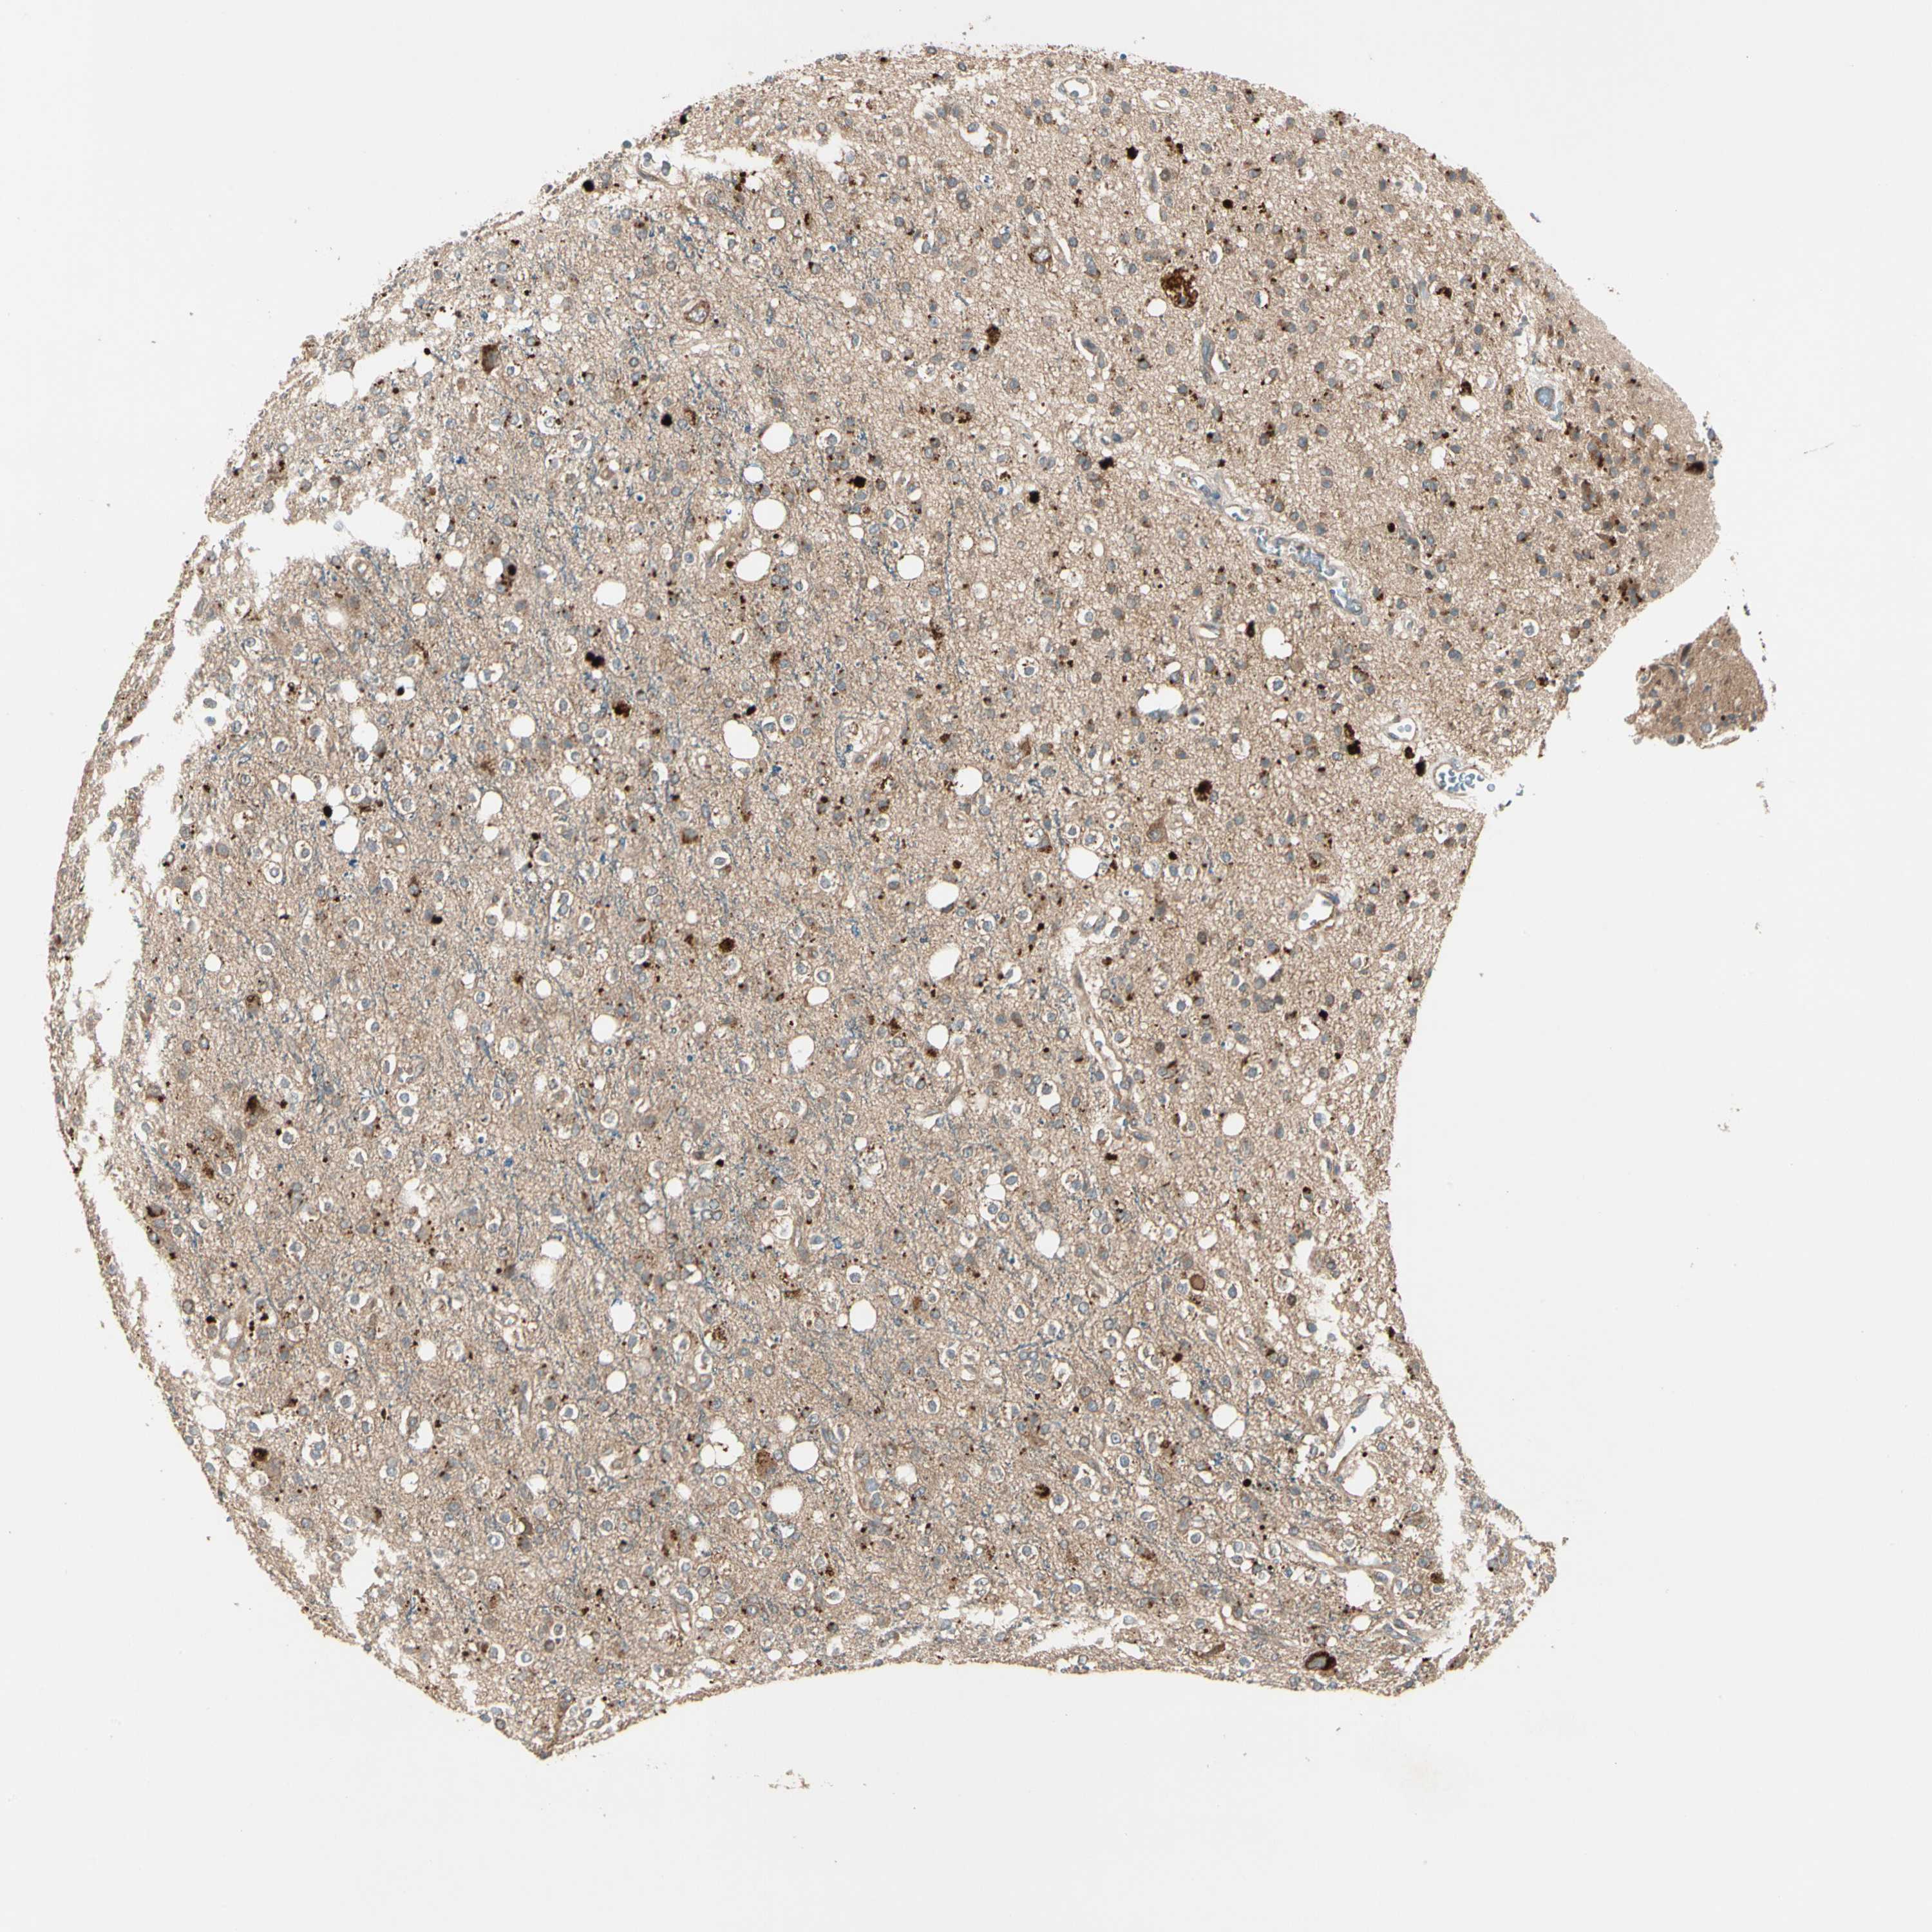

GLIOMA - Protein expressioni

A mouse-over function shows sample information and annotation data. Click on an image to view it in a full screen mode. Samples can be filtered based on level of antibody staining by selecting one or several of the following categories: high, medium, low and not detected. The assay and annotation is described here.

Note that samples used for immunohistochemistry by the Human Protein Atlas do not correspond to samples in the TCGA dataset.

Antibody stainingi

Antibody staining in the annotated cell types in the current human tissue is reported as not detected, low, medium, or high, based on conventional immunohistochemistry profiling in selected tissues. This score is based on the combination of the staining intensity and fraction of stained cells.

Each image is clickable and will lead to virtual microscopy that enables deeper exploration of all samples and also displays staining intensity scores, fraction scores and subcellular localization as well as patient and tissue information for each sample.

Antibody HPA007982

Antibody HPA011933

Staining

High

Medium

Low

Not detected

Intensity

Strong

Moderate

Weak

Negative

Quantity

>75%

75%-25%

<25%

None

Location

Nuclear

Cytoplasmic/membranous

Cytoplasmic/membranous,nuclear

Glioma, malignant, High grade

Glioma, malignant, Low grade